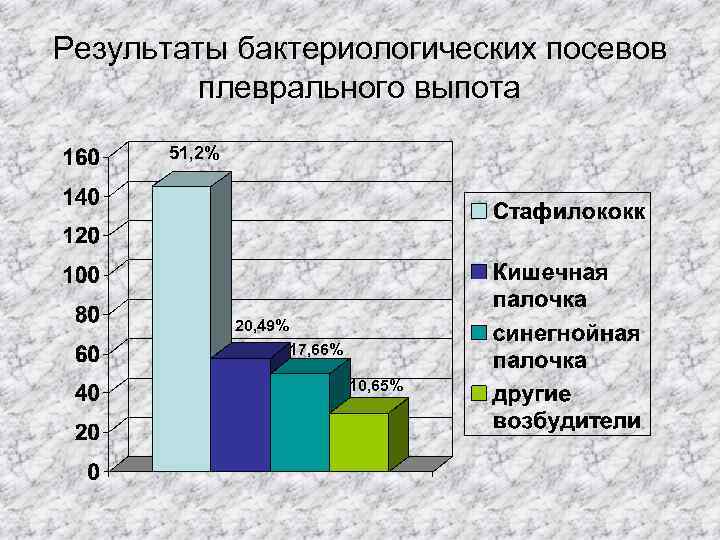

Результаты бактериологических посевов плеврального выпота 51, 2% 20, 49% 17, 66% 10, 65%

Результаты бактериологических посевов плеврального выпота 51, 2% 20, 49% 17, 66% 10, 65%